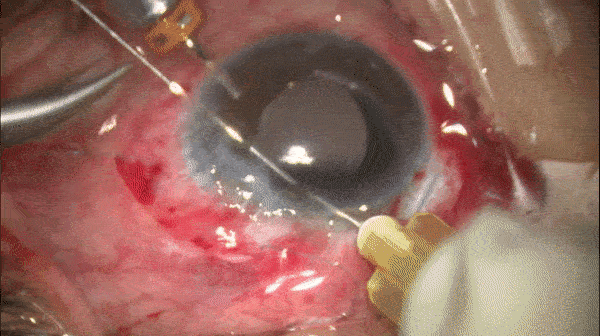

Step 6

再次采用上述方式在对侧襻上完成改良cow-hitch knot

开睑器怎么用术说睛彩 | 金海鹰教授:使用8-0缝线的无巩膜瓣人工晶体固定手术_https://www.jmylbn.com_新闻资讯_第7张